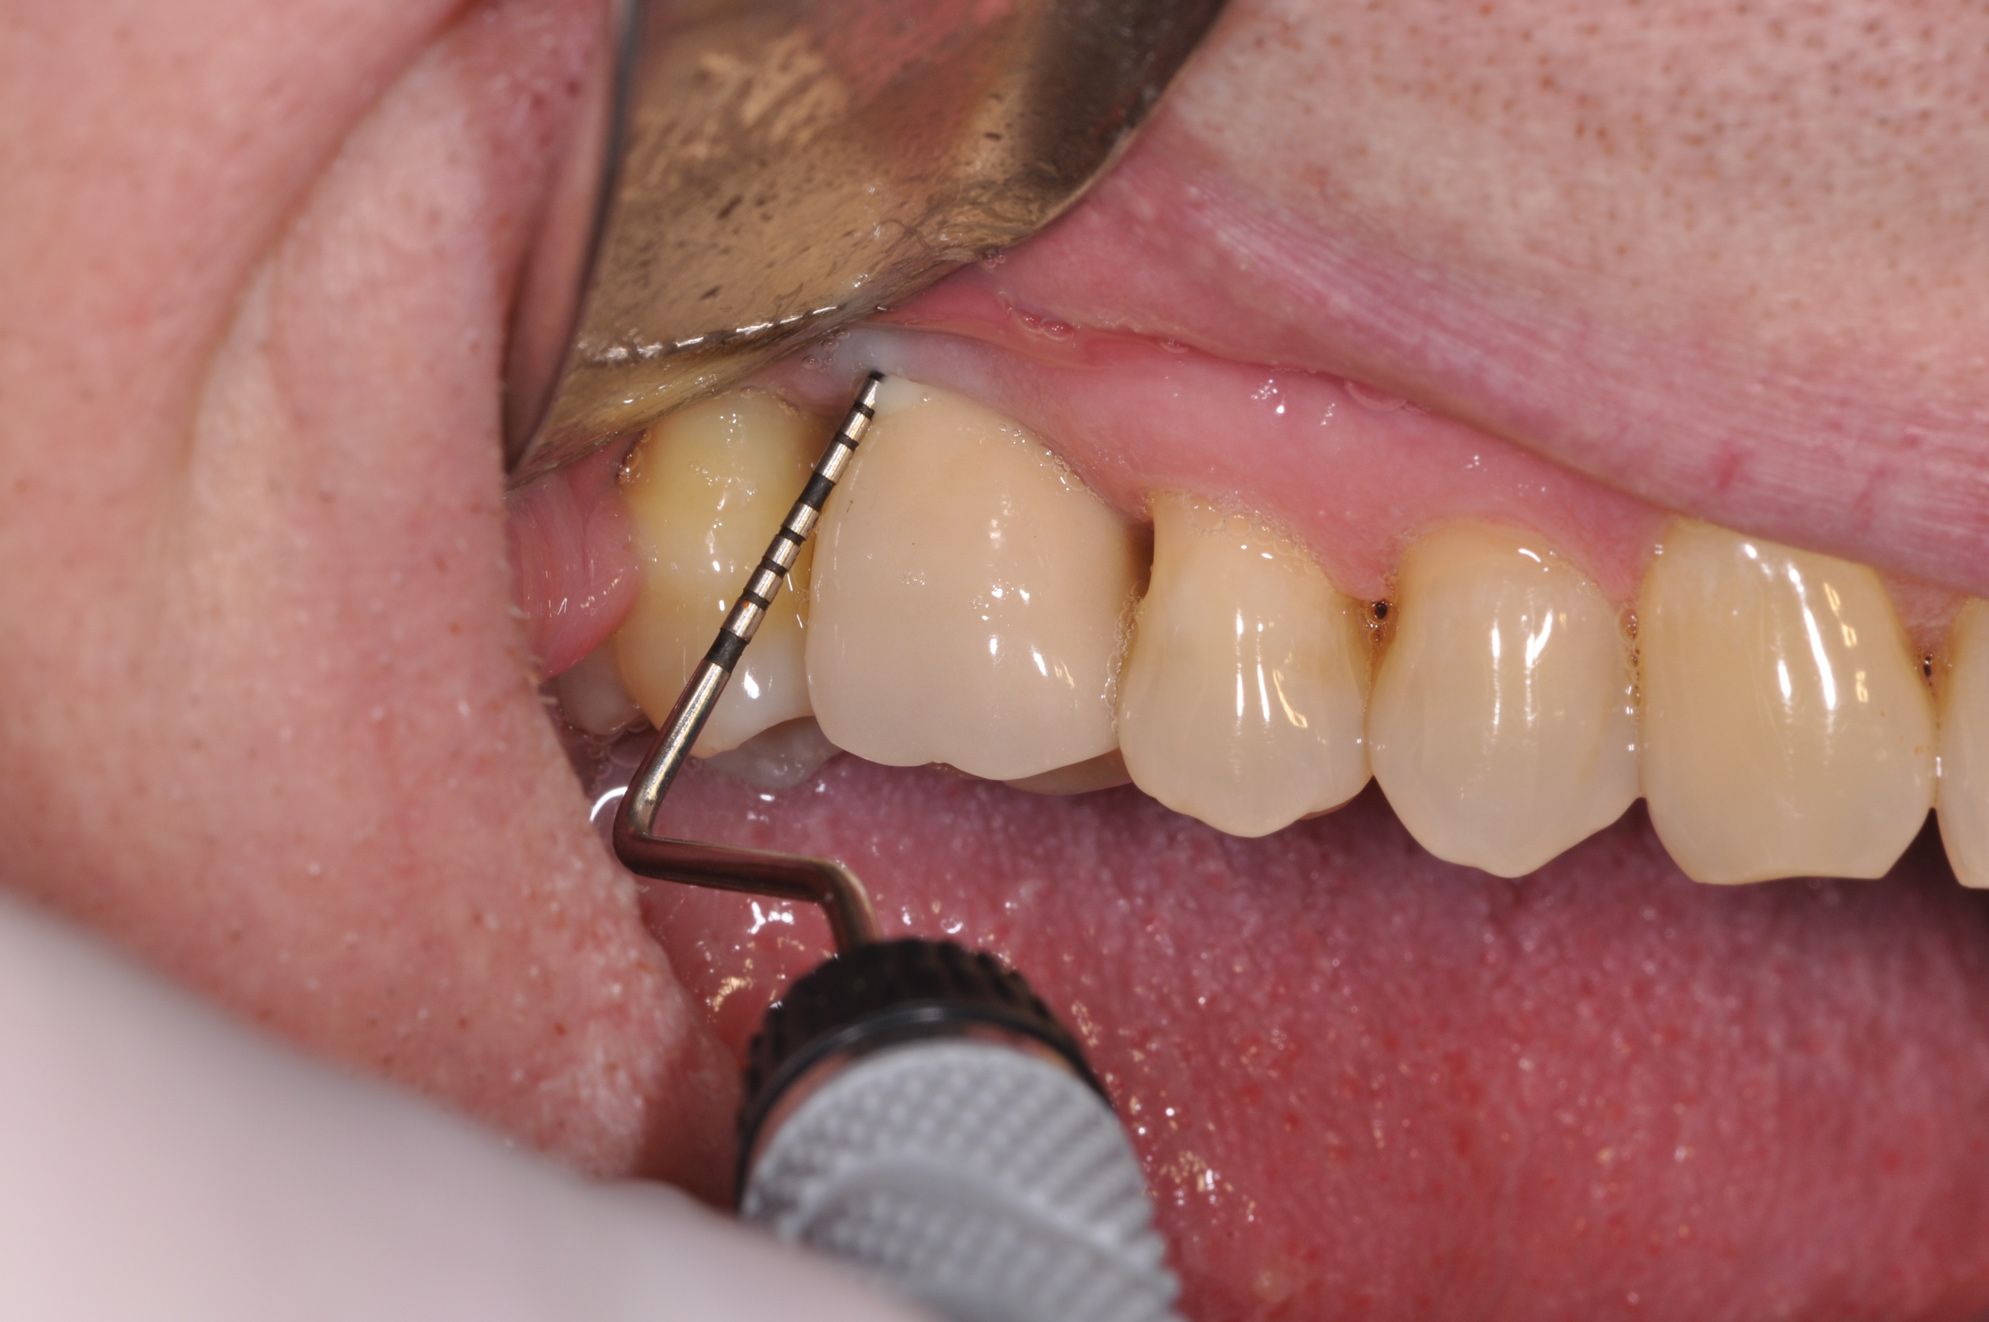

Following the diagnosis of peri-implantitis (Figure 5 and Figure 6), an initial evaluation of the affected implant fixture should be made to establish the rationale for treatment and whether removal of the implant is indicated. Although nonsurgical treatment of peri-implantitis may not always be successful, it should always precede surgical therapy, as this will provide the clinician time to assess the patient's oral hygiene status and response to therapy.22 The primary goal of surgical treatment of peri-implantitis is the decontamination of the denuded implant surface. Multiple surface decontamination protocols have been described in the literature; however, to date, none have shown superiority.23

Fig 5. In this patient, deep probing depths, suppuration, and bleeding on probing were identified.

Figure 5